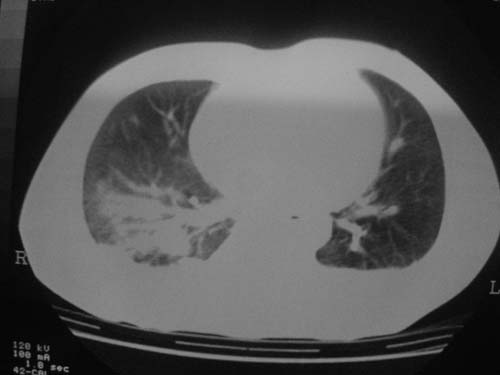

这是第三天拍的片子.